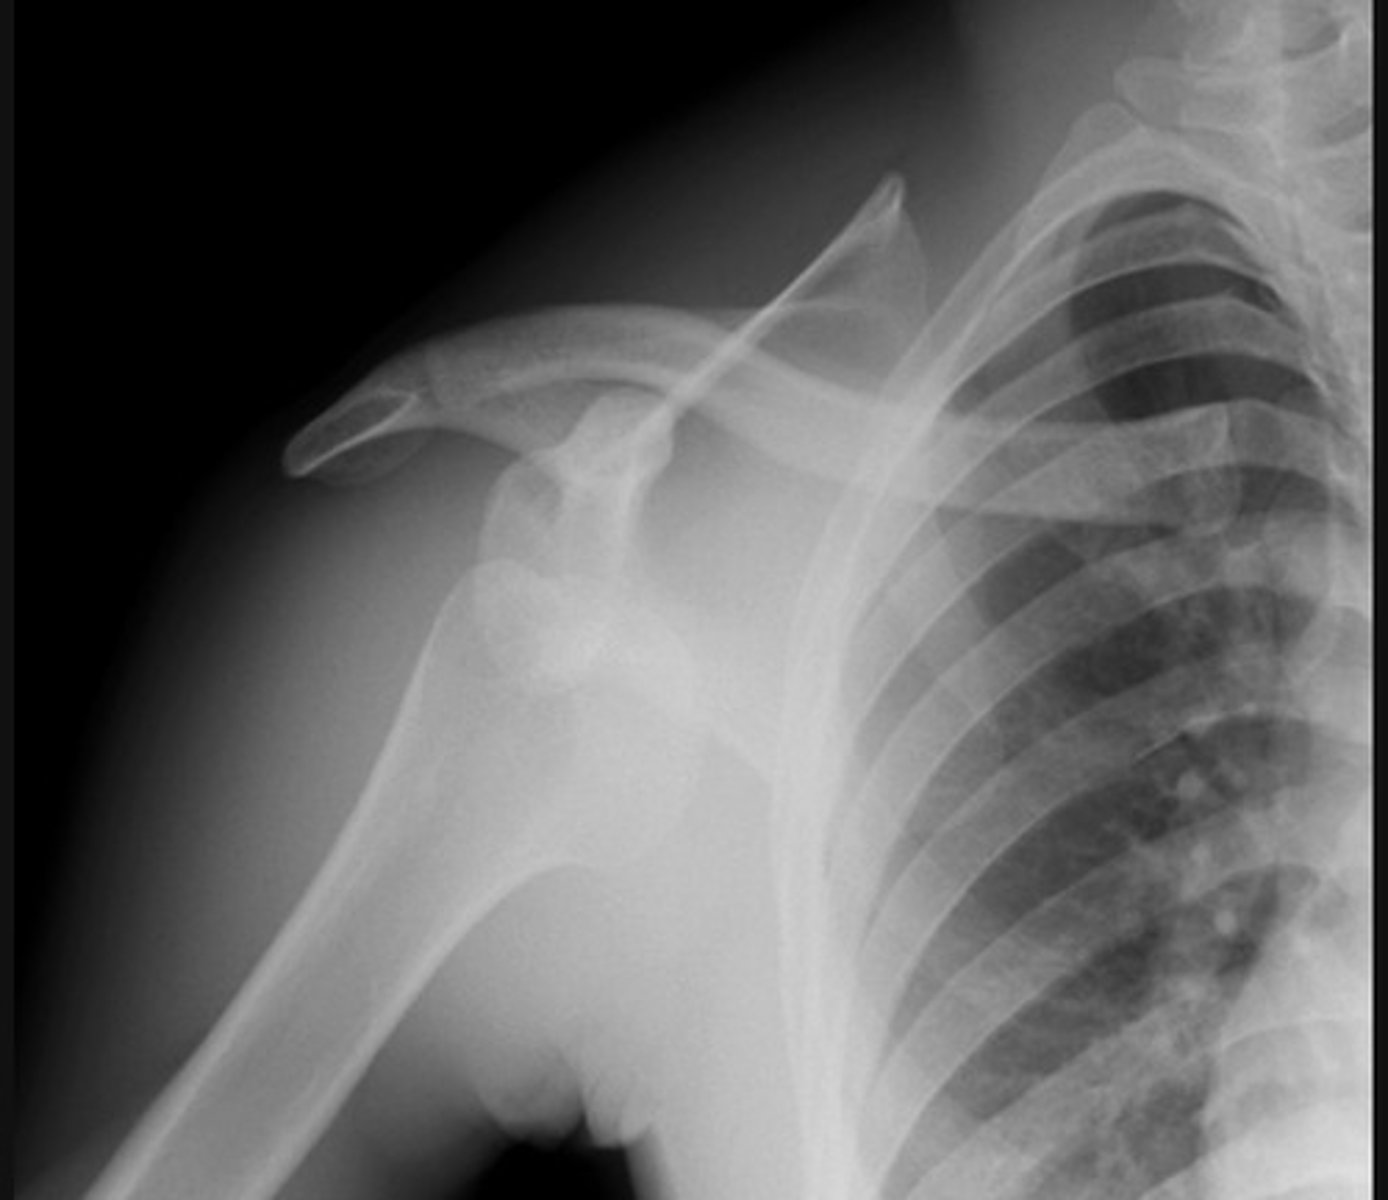

The distal component of this clavicle fracture is inferiorly displaced - pulled down by the weight of the arm

The inferior edge of the acromion is inferiorly displaced and is no longer in line with the inferior edge of the distal clavicle

The distal component of this clavicle fracture remains aligned with the proximal clavicle